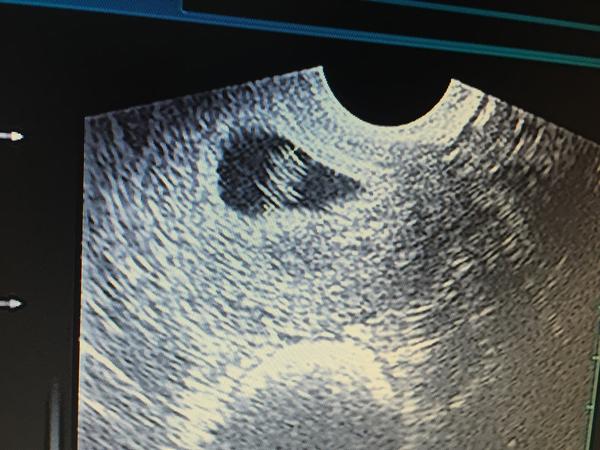

@vandica ja som bola v pondelok a videl len zvysenu sluznicu

@majba na odberoch som bola dnes, výsledky klasika o dva týždne a na ultrazvuku bolo vidieť len takú malinkú bodku 2,5 mm. Zatial také nič 🙂